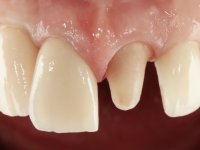

Na primeira intervenção foi proposto à paciente uma coroa total com infraestrutura em Zr revestida por cerâmica. O facto do dente ter um tratamento endodôntico foi determinante nesta opção. Na segunda intervenção, foi proposto a remoção dos dois implantes. No implante colocado no local do dente1.2 seria feita uma regeneração óssea simultânea à colocação do novo implante. Contando com a inevitável retração gengival na zona cervical da coroa do 1.1, foi também proposto refazer a coroa do dente 1.1. Foi também adiantado que por questões de simetria, se fosse necessário, também poderia ter que se intervir no dente 2.2. Assim, na zona antero-superior, teríamos coroa aparafusada sobre um novo implante colocado no 1.2, nova coroa no1.1 e uma faceta ou coroa no dente 2.1 se necessário. No implante colocado na zona do 4.6, propomos removê-lo, colocar um novo implante, posteriormente reabilitado com uma coroa aparafusada.

Segunda Fase.

Após 5 anos da primeira intervenção, a paciente surge na consulta com uma peri-implantite nos implantes colocados no local dos dentes 1.2 e 4.6. Começamos por abordar a peri-implantite no local do dente 2.2. Foi feita uma ponte provisória de laboratório em acrílico com 2 elementos. O dente 1.1 como pilar e o 1.2 como pôntico, este último apresentava um apoio distal. A coroa do 1.2 foi removida do coto com um corte longitudinal feito com turbina e depois foi fraturada com um mini luxador. O coto foi de seguida desaparafusado do implante. Fez-se o mesmo procedimento para remover a coroa do 1.1. O dente 1.1 foi re-preparado e a ponte provisória foi rebaseada em boca com acrílico autopolimerizável. Feito o correto acabamento e polimento da provisória foi feita a sua cimentação temporária com cimento de policarboxylato. Numa consulta posterior. foi feita a remoção da ponte provisória, feita a cirurgia para explantação do implante, colocou-se um novo implante e fez-se a regeneração óssea da zona com uma membrana não reabsorvível. 3 meses após foi removida a coroa do implante colocado no 4.6. Foi feito um corte horizontal com turbina na zona cervical e com um mini luxador descolou-se a coroa do coto. Após este procedimento fez-se a explantação do implante. Após 6 meses foi colocado um novo implante no local do 4.6. Após a osteointegração foi feita a impressão com a técnica de moldeira aberta e foi confecionada em laboratório uma coroa aparafusada sobre o implante. Aprovada pela paciente foi apertada definitivamente em boca. Após 1 mês removemos a ponte provisória antero-superior, reforçamos o dente 1.1 com um poste intra- radicular e reconstruimos o coto com uma resina de polimerização dual. Nessa mesma consulta expomos o implante colocado no 1.2 e fizemos uma impressão pela técnica de moldeira aberta com silicone de dupla viscosidade e presa rápida. No laboratório foi feita uma ponte provisória de 2 elementos, aparafusada sobre o implante e cimentada sobre o dente. A primeira ponte provisória foi removida e colocada a segunda aparafusada sobre o implante. A linha de acabamento cervical do 1.1 foi rebaseada com resina composta durante o aperto do parafuso do implante. Depois foi removida, foram feitos os acabamentos e finalmente apertada sobre o implante e cimentada temporariamente sobre o dente. Após 2 meses de maturação dos tecidos moles em função do perfil de emergência criado pela nova ponte provisória, pudemos avaliar a estética conseguida em conjunto com a paciente. Neste longo processo o dente 2.1 teve que fazer um tratamento endodôntico. Decidiu-se assim fazer também uma coroa no dente 2.1.O dente 2.1 foi preparado na mesma consulta em que se fez a impressão ao implante. A ponte provisória foi utilizada para individualizar a peça de transferência, copiando o seu perfil de emergência e em seguida foi realizado o afastamento gengival com caolino. A impressão foi feita com a técnica de moldeira aberta com silicone de dupla viscosidade e presa rápida. Após a escolha da cor, a impressão foi enviada  para o laboratório onde foram confecionadas 2 coroas  com infraestrutura em Zr. revestidas a cerâmica para os dentes 1.1 e 2.1 e uma coroa aparafusada sobre o implante no dente 1.2. O trabalho final foi aprovado pela paciente e foi colocado definitivamente em boca. A coroa sobre o implante foi aparafusada com 35 N e as coroas foram cimentadas com cimento de ionómero de vidro reforçado com resina.